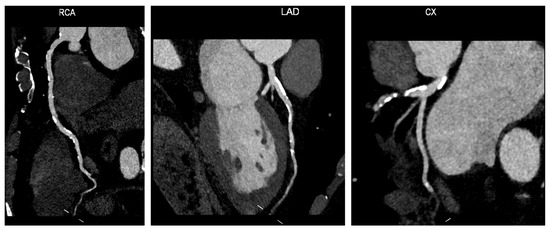

4. Supra-Aortic Trunks Ultrasound in Cardiovascular Prevention